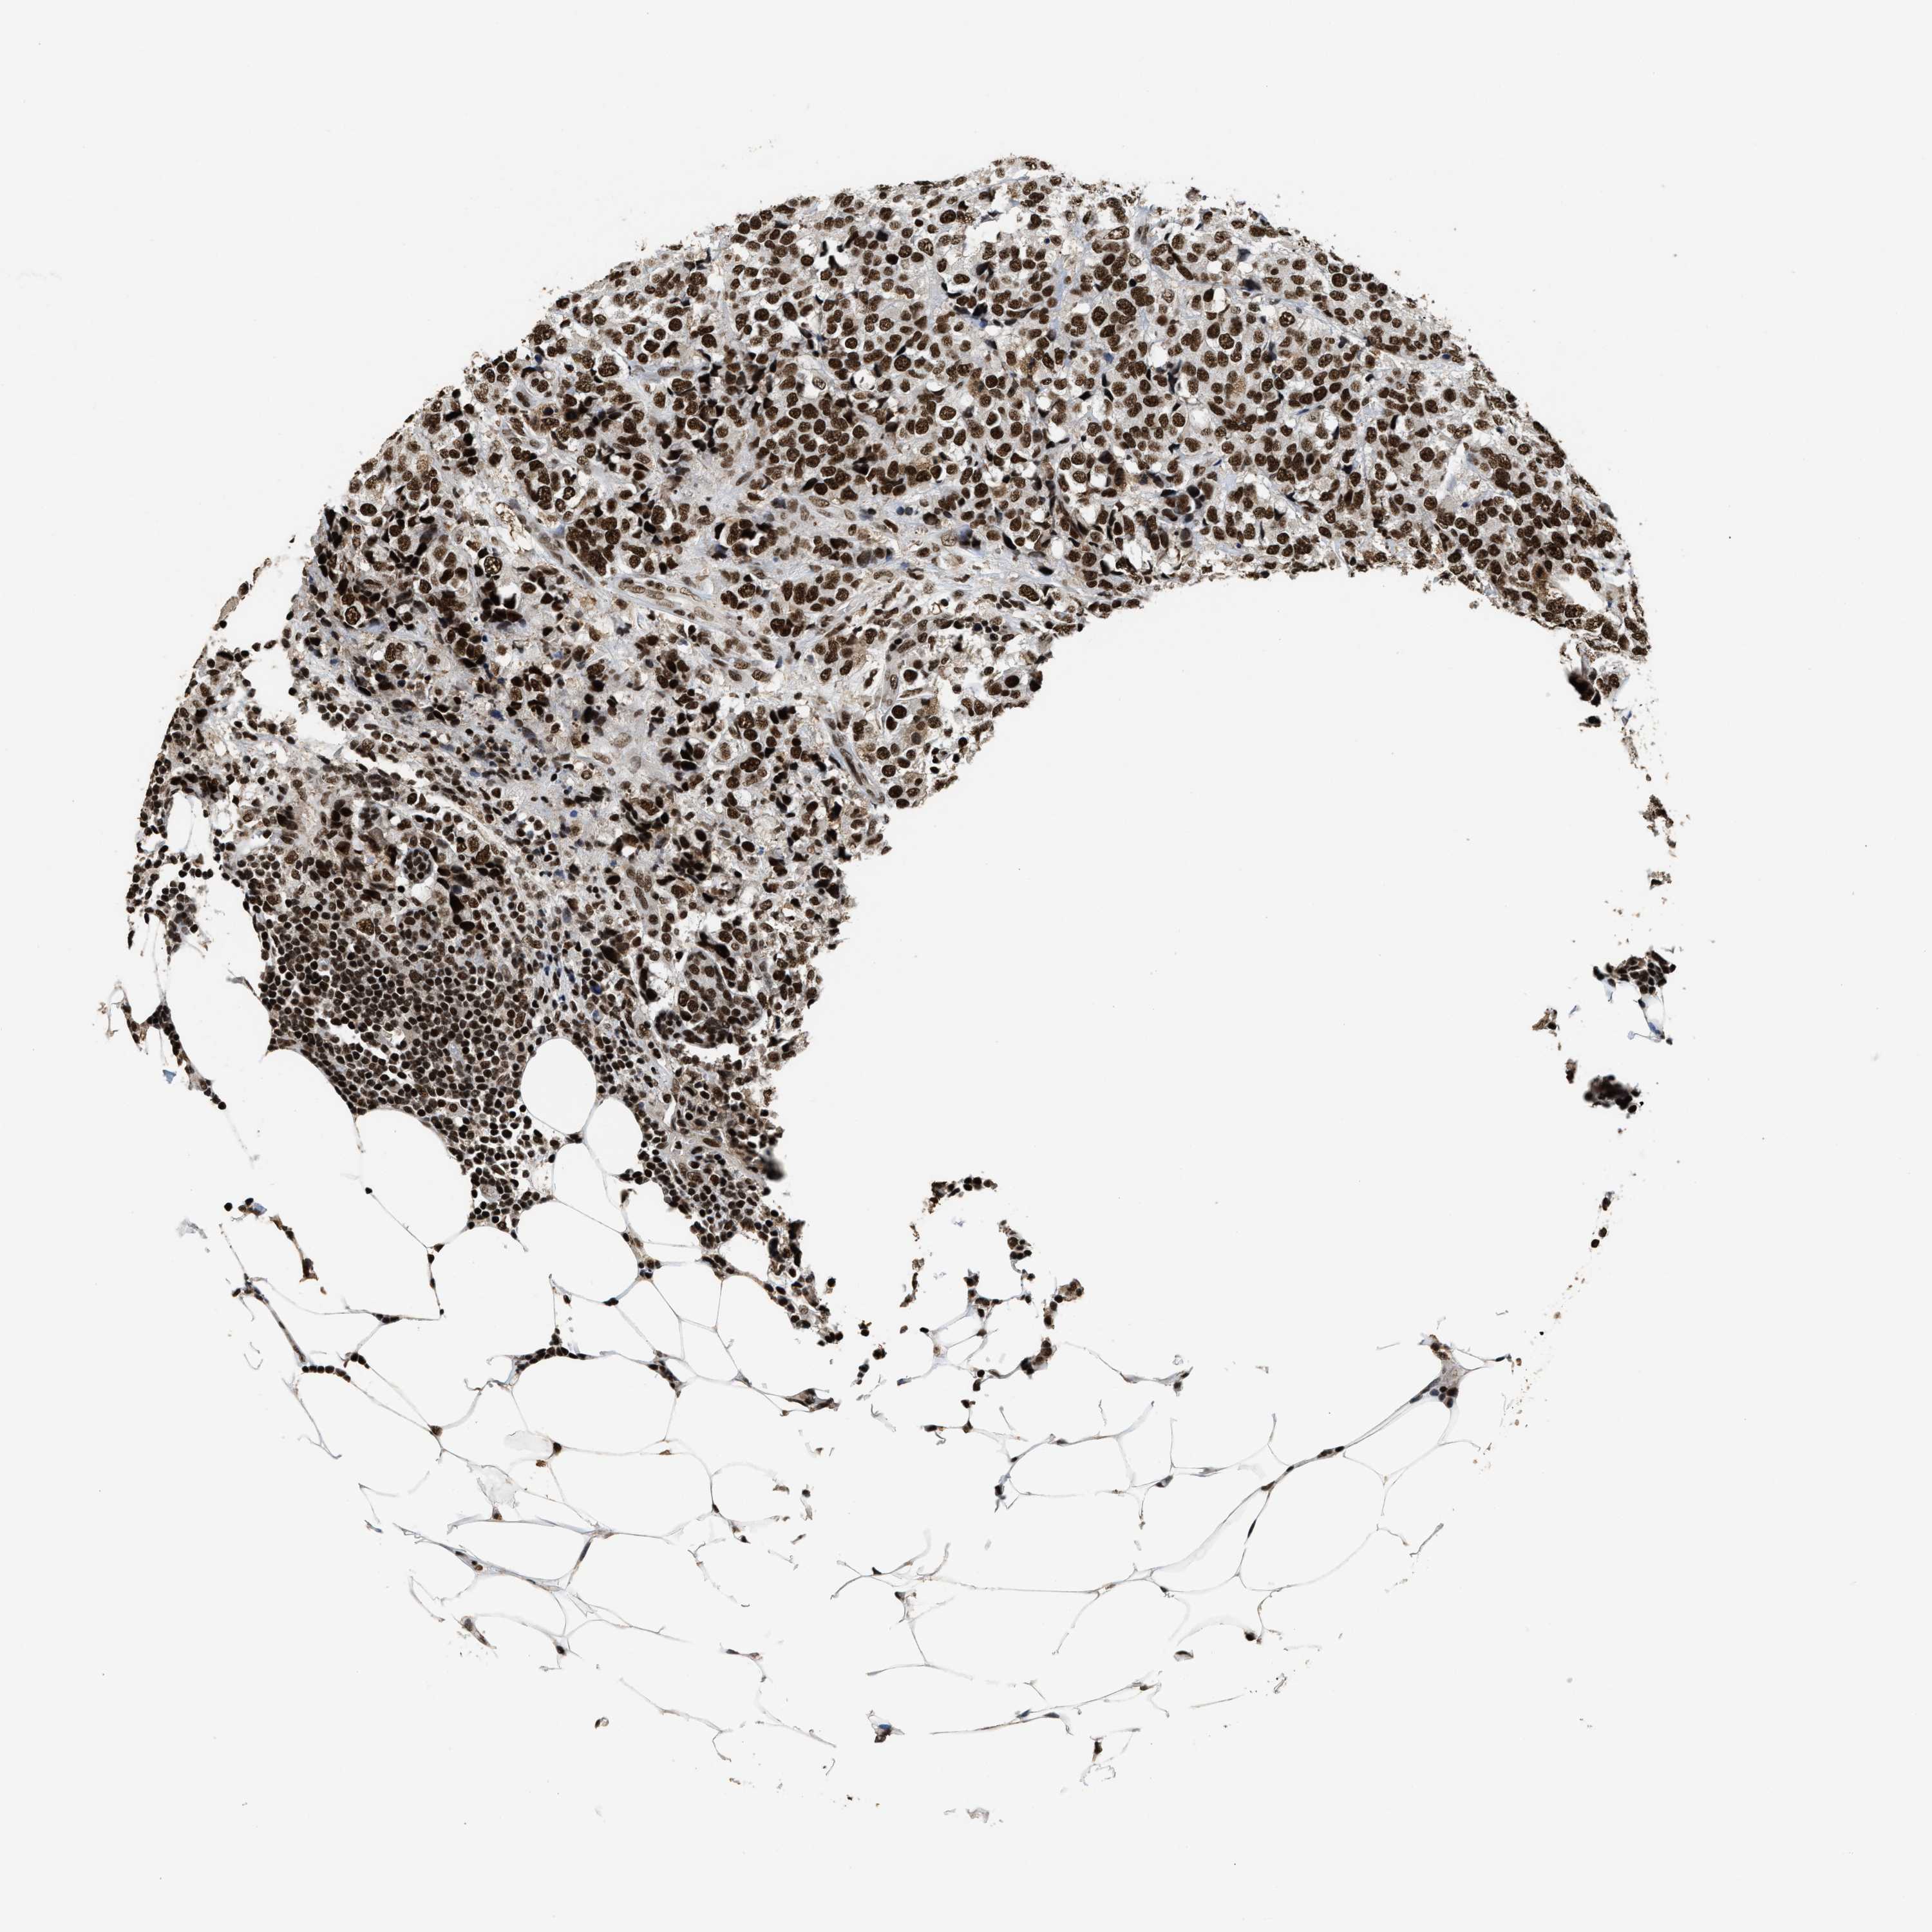

CANCER BREAST CANCER Show tissue menu

BRCA TCGA BRCA VALIDATION PROTEIN EXPRESSION